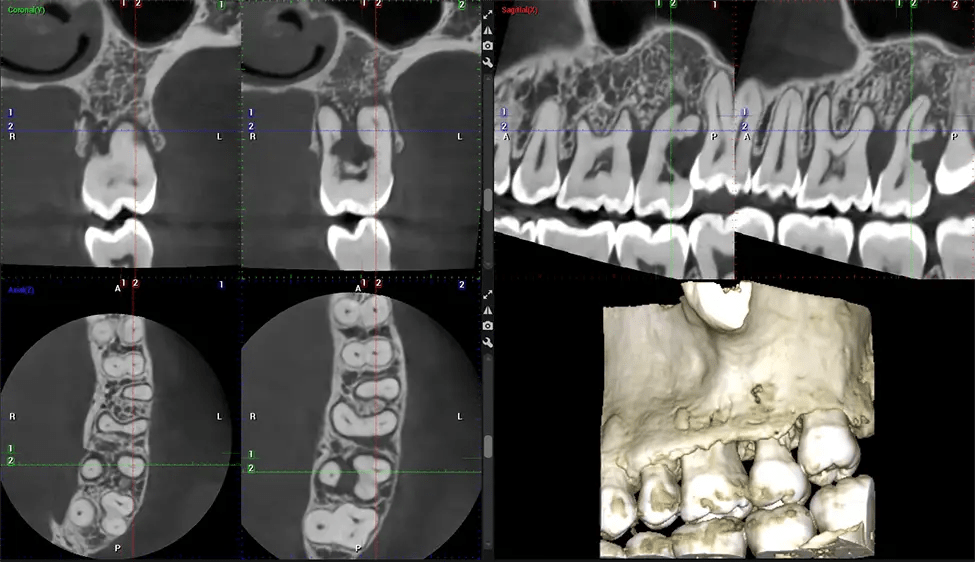

This 3D scan, called cone beam computed tomography, gives your dentist a more complete image of your oral anatomy and disease processes than a traditional X-ray. Unlike conventional X-rays, which capture a 2D image of your mouth from various angles, a 3D scan takes multiple digital X-rays for one image. It provides a complete view of your jaw, teeth, nerves, and soft tissues. This enhanced view allows dentists to detect minor issues not visible in traditional 2D scans, such as impacted wisdom teeth or bone fractures in the sinus cavity.

Another significant benefit is that 3D imaging provides more precise images of your bone structure. These images are more detailed, providing you with a more accurate diagnosis. An accurate diagnosis means better treatment for you.

After the scanning process, the captured X-ray images are processed by the CBCT software, which applies algorithms to reconstruct a detailed 3D image of the scanned area. The software compiles these individual X-ray images and creates a digital 3D representation of the patient’s anatomy. The reconstructed 3D CBCT image can be viewed and analyzed by the dentist or radiologist. This image can be manipulated, rotated, and zoomed in or out to examine specific structures and evaluate the patient’s condition.

Our patented SCARA technology enables doctors to capture True Extraoral Bitewings that are as accurate at detecting caries as a 2D bitewing series, but with half the radiation dose. With our bitewings, doctors can view the apices of teeth on both jaws providing a more comprehensive view of the patients’ anatomy.